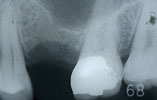

CASE4

上の前歯1本だけ失った場合 審美的回復

インプラント埋入前

インプラント埋入後

インプラントに

セラミッククラウンを装着

上の前歯1本だけ失った場合、通常両隣りの歯を削ってブリッジを入れますが、インプラント治療によって、健康な歯を削ることなく、審美的にも回復しました。。